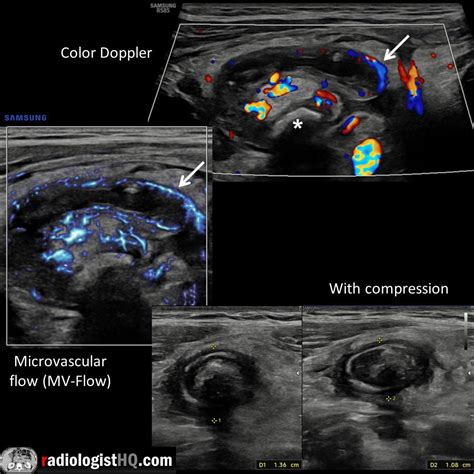

• Hyperemia: Increased blood flow to the appendix, which can be detected using Doppler ultrasound, is another sign of inflammation.

• Image Acquisition: The radiologist moves the probe to capture images of the appendix from different angles. Doppler ultrasound may be used to assess blood flow.